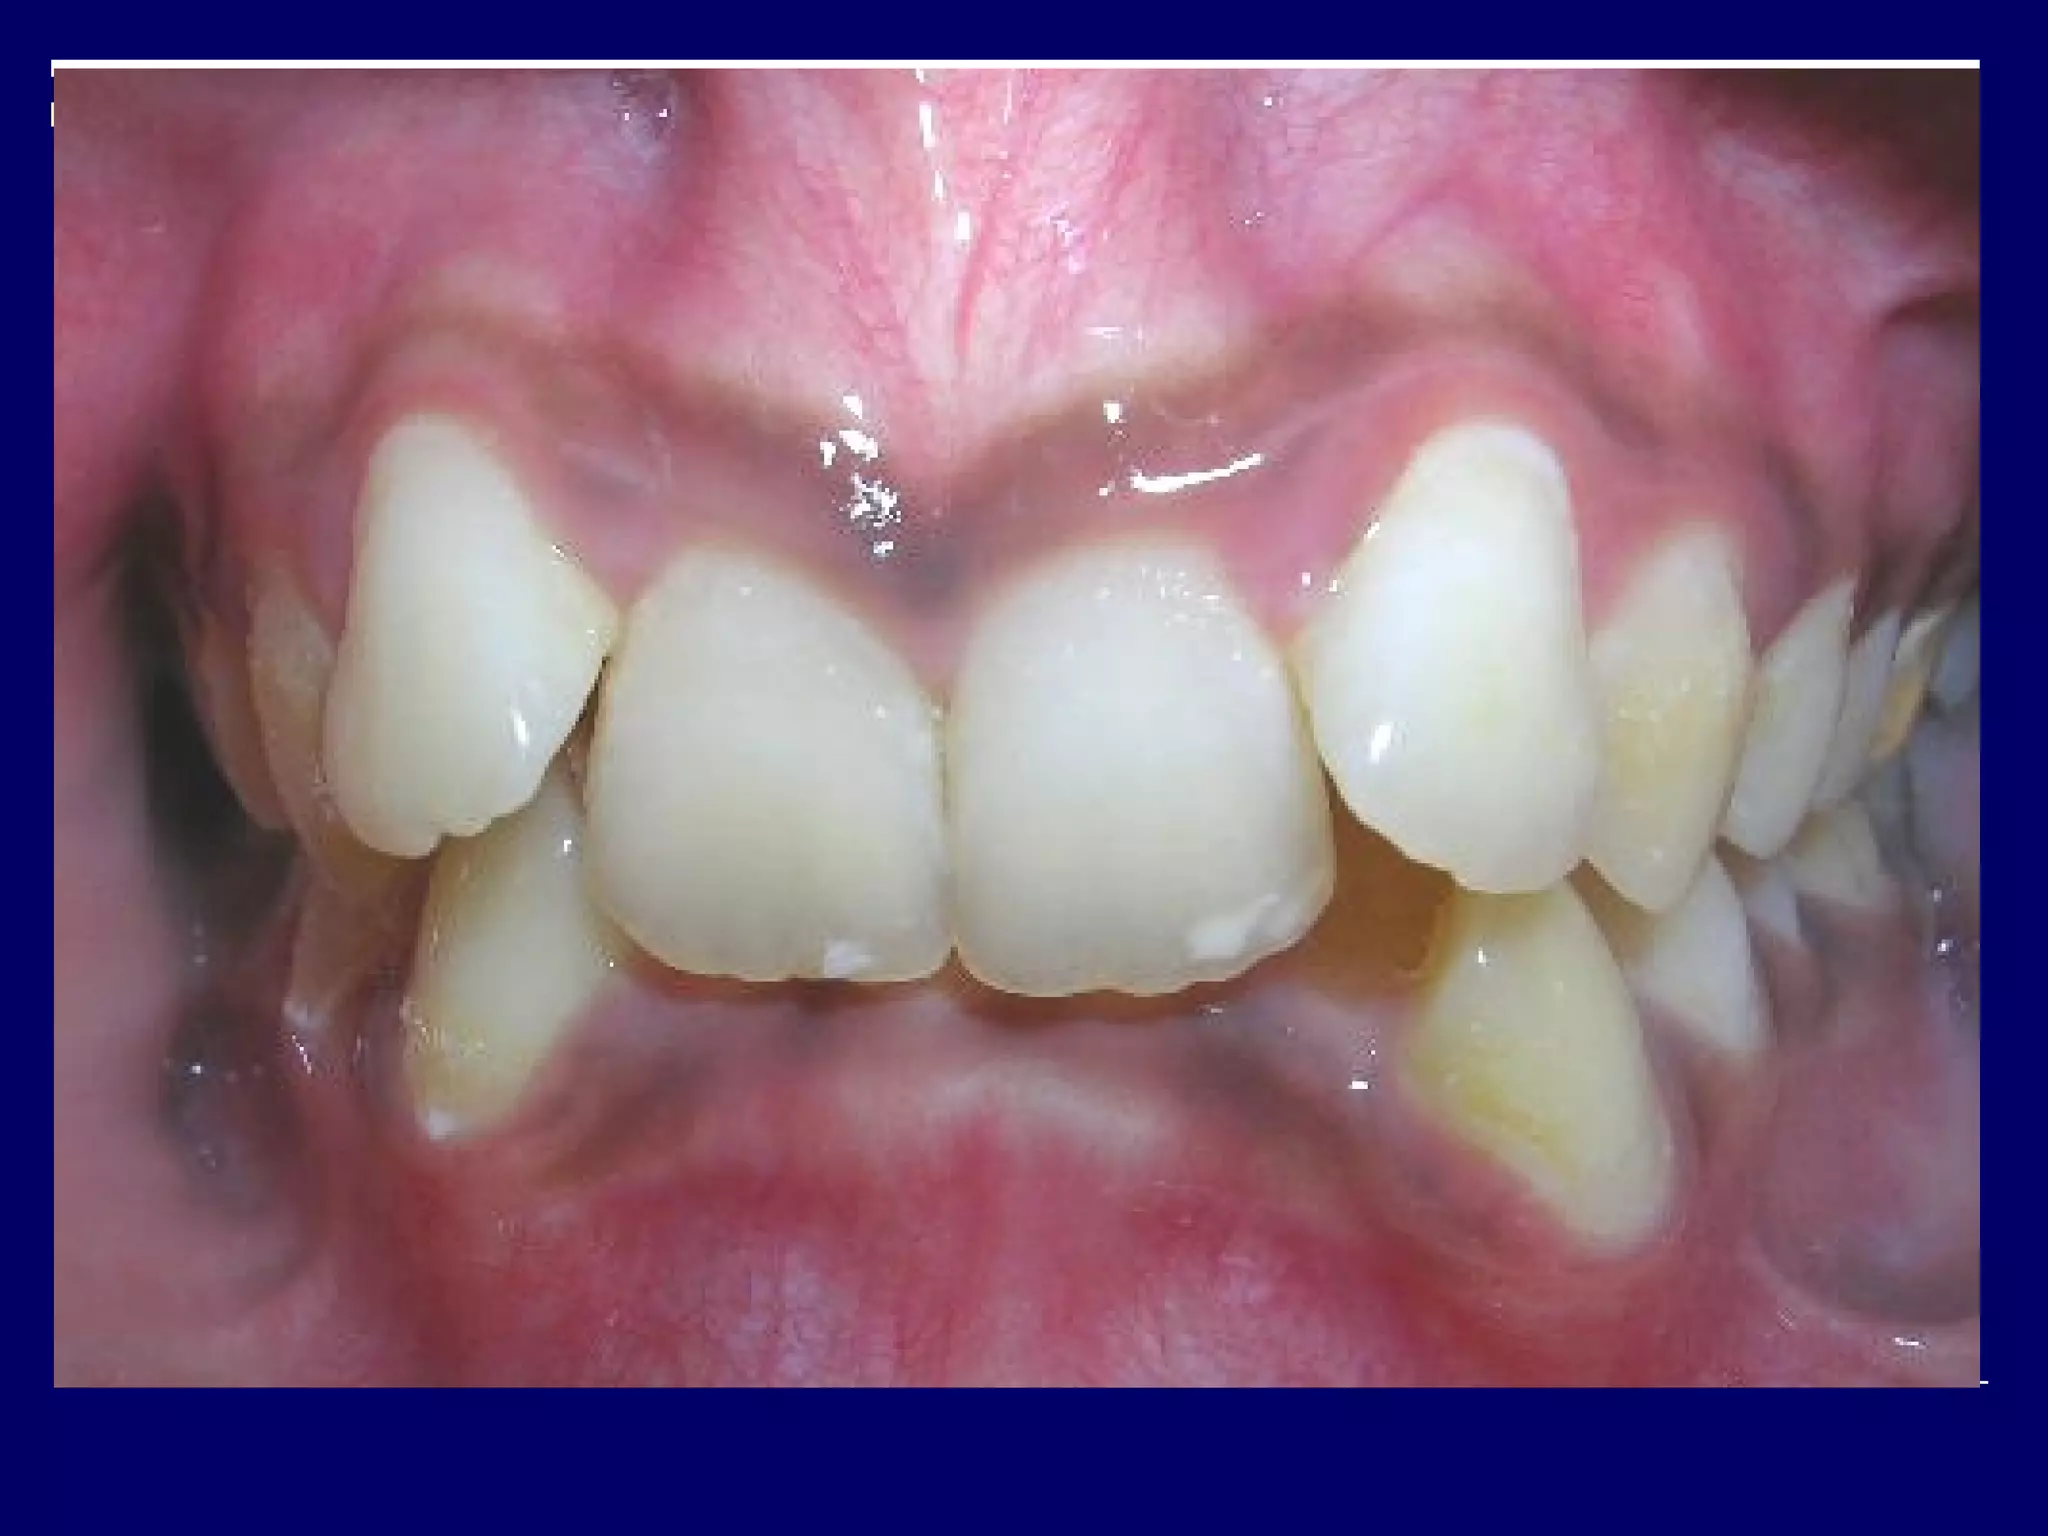

Class II division 1 malocclusion

Molar relation is class II

The upper insisors are proclined.

Class II division1 malocclusion Molar relation is class II The upper insisors are proclined.